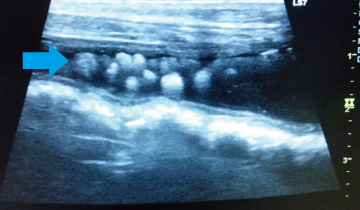

血尿を主訴に来院したプードルです。レントゲン検査と超音波検査で膀胱結石と診断しました。

矢印で示したのが結石です。